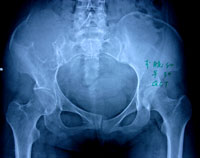

疾病描述:巨細胞瘤很可能起源於骨髓結締組織間充質細胞,以基質細胞核和多核巨細胞為主要結構,是一種潛在惡性或介於良好惡之間溶骨性腫瘤。好發年齡20-40歲,性別差異不大,好發部位為股骨下端和脛骨上端。X線片表現:骨骺處有局限的囊性改變,一般呈溶骨性破壞,也可有“肥皂泡”樣改變,其擴展一般為軟骨所限。不破入關節,少有骨膜反應,腫瘤範圍清楚,初發時病變在骨骺內旁側,發展後可占骨端的全部,骨皮質膨脹變薄,有的可以穿破,進入軟組織。X線片可顯示其一般特點,但仍不足以確診。主要的症狀為疼痛和腫脹,與病情的發展相關,局部包塊壓之有桌球樣感覺,病變的關節活動受限。骨巨細胞瘤多發生於四肢長骨的骨骺端,尤以股骨下端及脛骨上端為多見,約占半數左右,其次為橈骨下端、尺骨下端或肱骨上端等部位。長骨以外則以脊椎為多見。

X線主要表現為骨端變心位溶骨性破壞而無滑膜反應,病灶骨皮質膨脹變薄,呈肥皂泡樣改變。

X線片表現:骨骺處有局限的囊性改變,一般呈溶骨性破壞,也可有“肥皂泡”樣改變,其擴展一般為軟骨所限。不破入關節,少有骨膜反應,腫瘤範圍清楚,初發時病變在骨骺內旁側,發展後可占骨端的全部,骨皮質膨脹變薄,有的可以穿破,進入軟組織。X線片可顯示其一般特點,但仍不足以確診。